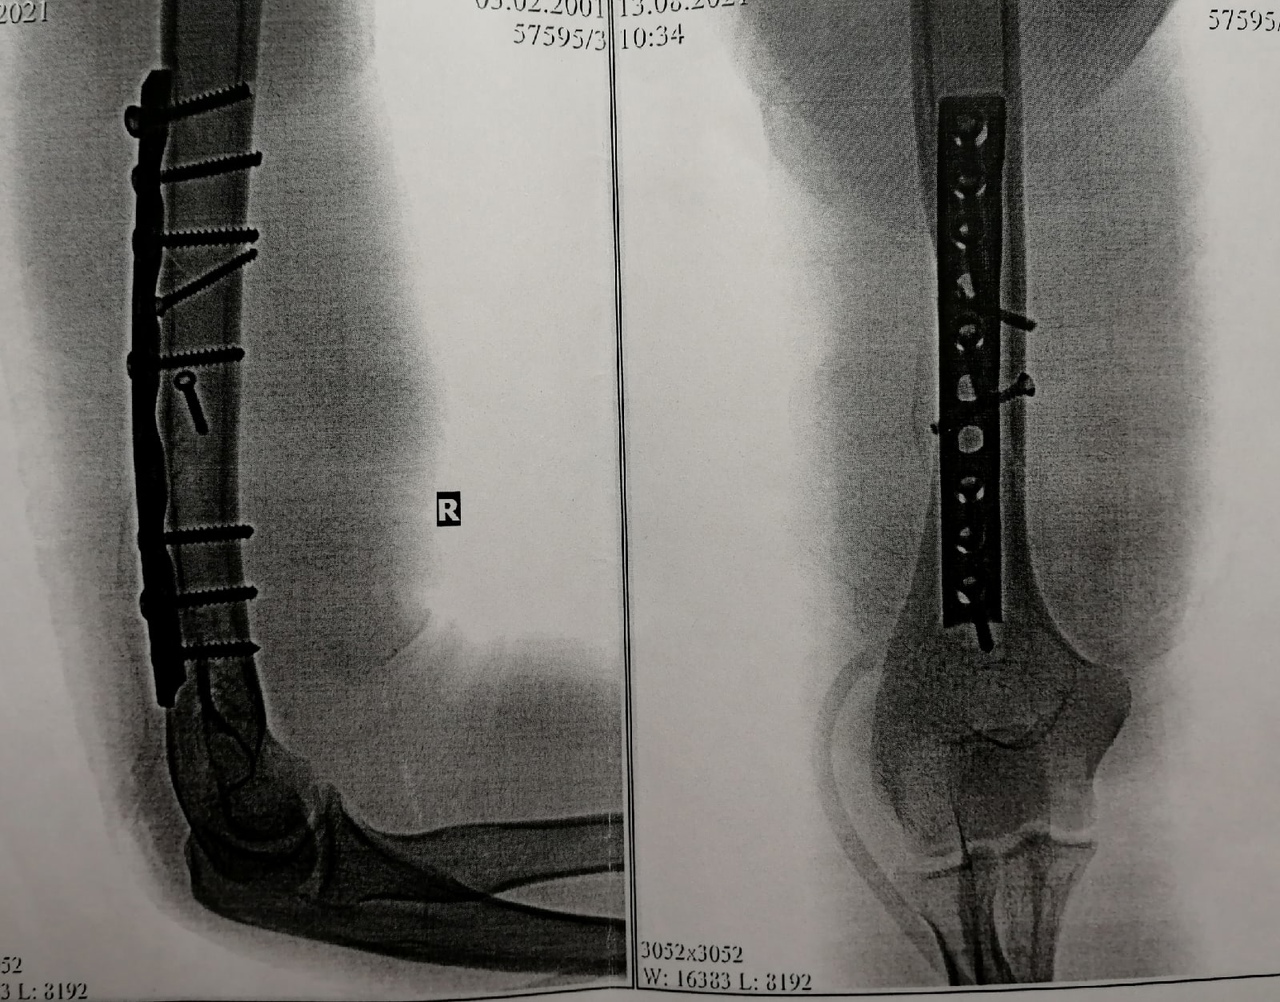

Проверял прочность костей после происшествия, когда подтягивался на турнике и сломалась рука, когда висел, а именно был: закрытый перелом нижней трети диафиза плечевой кости со смещением осколков. После чего провели остеосинтез и поставили пластину и винты. Фото прикладываю. Что можно сказать по данной истории болезни?

Вам положена категория годности "В" по статье 81, пункту "в" Расписания болезней: "Неудаленные металлические конструкции (после остеосинтеза диафизарных переломов длинных костей, ключицы, надколенника) при отказе от их удаления", так как плечевая кость - это одна из длинных костей.